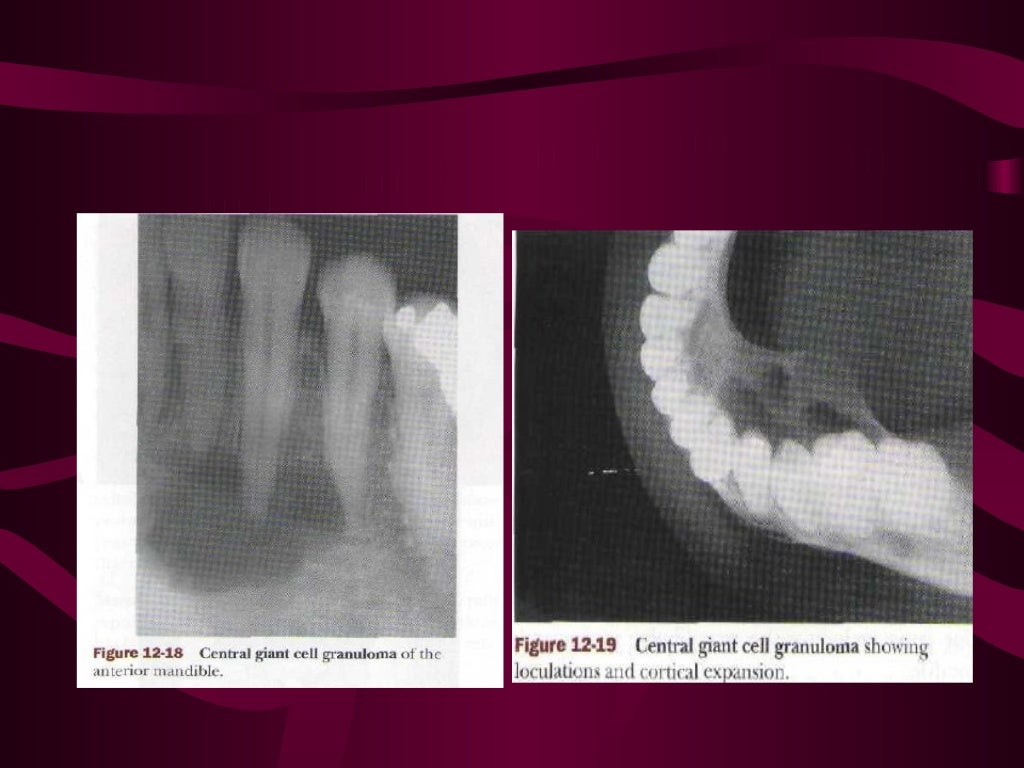

Giant cell lesion’s of jaw